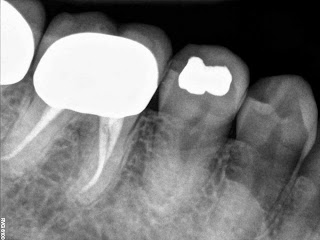

Root Canal Lower Molar First

Vital. Normal anatomy

All 3 canals had apical curvatures that rotaries wouldn’t curve around so had to hand file. They may have been stuck in a ledge formed from my overaggressive use of SX to open coronal though also. either way this took 2 hours and should have been about 1 hour.